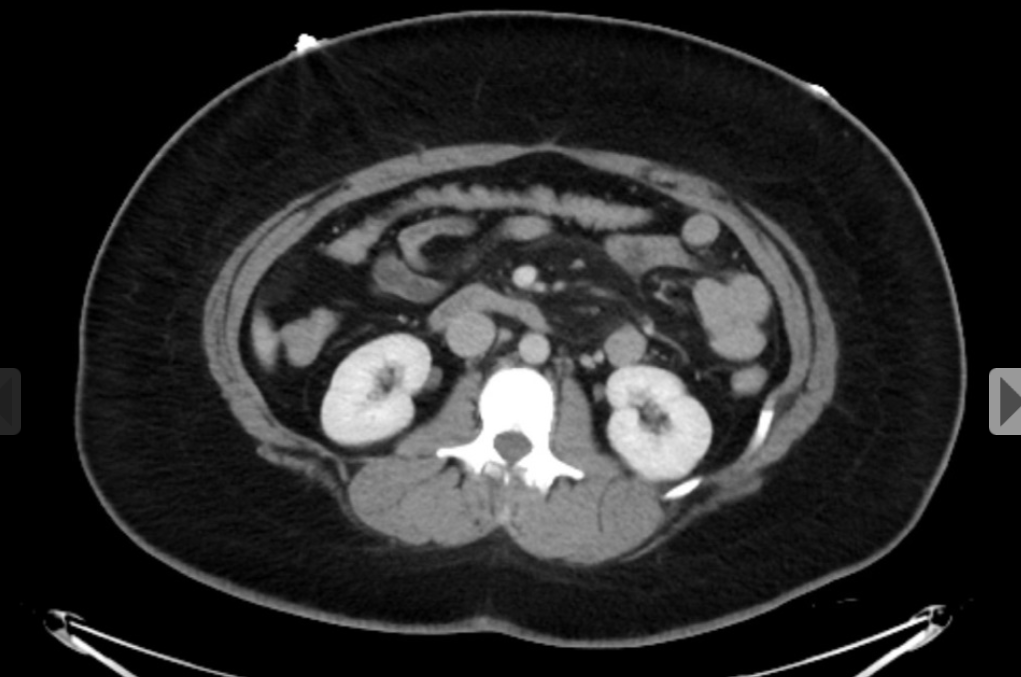

6 anos; vomitos

Má-rotação intestinal

Duodeno não cruza para a esquerda;

Intestino delgado fica enrolado no lado direito do abdome e o colon à esquerda.